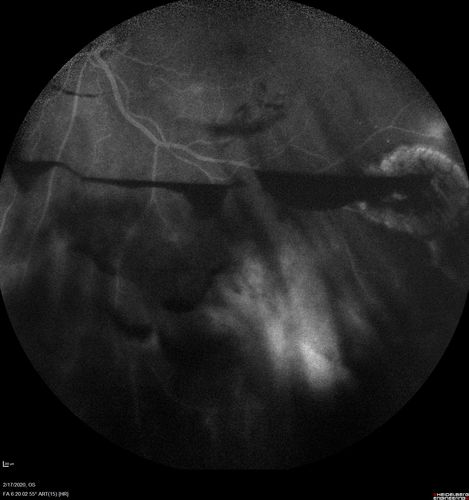

PDR and Vitreous Hemorrhage - High Risk Left Eye - Low Risk Right Eye

50 year old man with type I diabetes mellitus for 26 years. New Vitreous Hemorrhage in the left eye. Both eyes have NVE. Both also have foveal hypoplasia